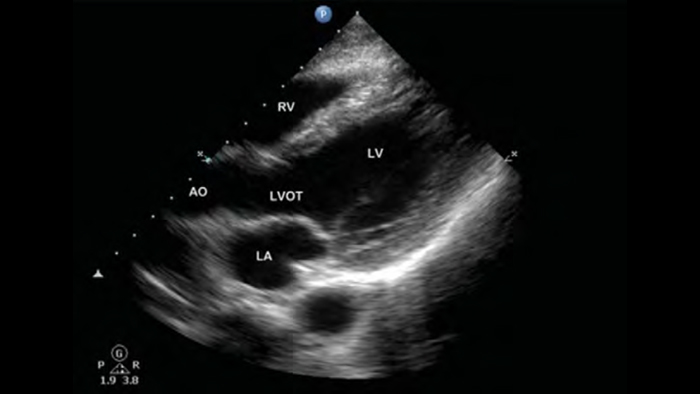

A patient with dyspnea

Pre-hospital point of care cardiac ultrasound: pulmonary embolism